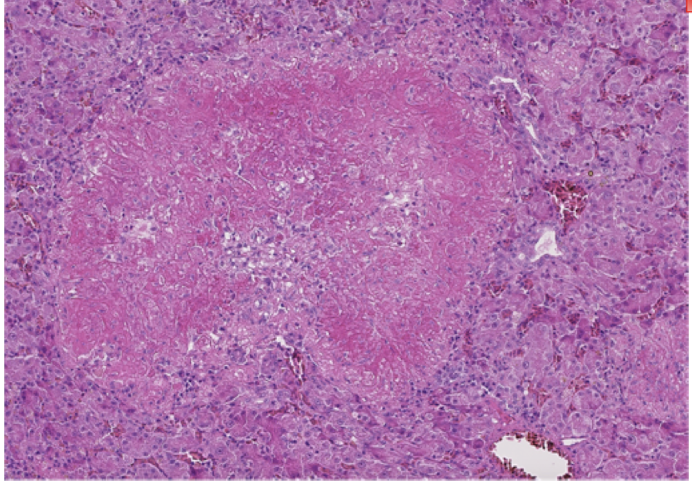

What is occuring in this histological image of a bird liver? What is the condition associated with it?

Psittacosis - Necrosis ( coagulative necrosis -> still has some cell shape/ sinus outlines)